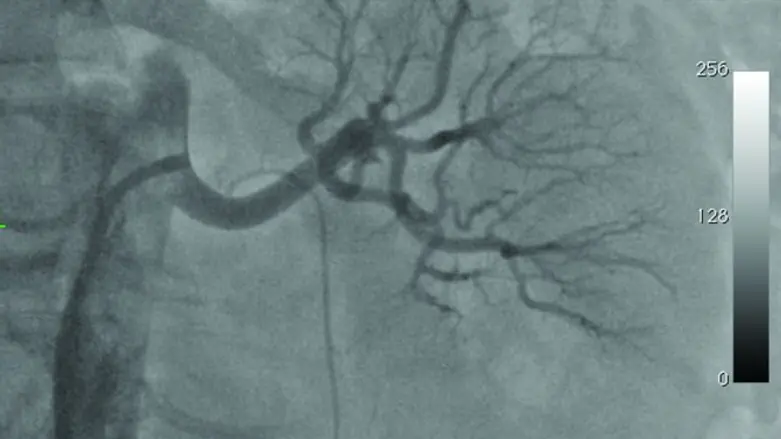

הפרוצדורה נעשית באמצעות צנתור בטשטוש דרך עורק המפשעה. הצנתר הספירלי נוגע בדפנות עורקי הכליה ומחמם אותם. כך למעשה משובשים העצבים הסמוכים לעורקי הכיליה מבלי לפגוע בעורקים עצמם.

היום בוצעה לראשונה פעולה לצריבת עורקי כליה בבית החולים הרצליה מדיקל סנטר. הפעולה עושה שימוש בטכנולוגיה ייחודית המאפשרת צריבה בטוחה ויעילה של סיבי העצב של הכיליה בשיטה שנבדקה בהצלחה במספר רב של מחקרים.